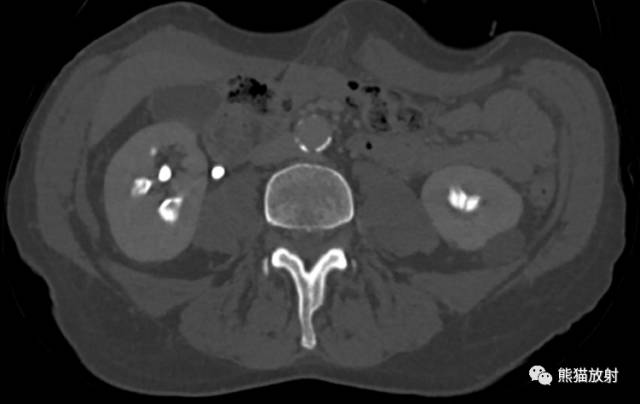

CT urogram (2017): Noncontrast images demonstrate multiple bilateral nonobstructing renal calculi, the largest measuring 6 mm in the right kidney. Some of the calcifications could represent nephrocalcinosis — for example, those in the upper pole of the right kidney. The kidneys show symmetric enhancement without suspicious renal mass. Multiple bilateral exophytic simple renal cysts are noted, the largest in the midpole of the right kidney measuring 3.6 x 4.3 cm. There are additional subcentimeter low-attenuation lesions that are too small to characterize. There is a “paintbrush sign” appearance to the renal medullae in keeping with a history of medullary sponge kidney. There is mild bladder wall thickening and trabeculation that may be related to chronic outlet obstruction. Further evaluation is deferred to cystoscopy.

CTU:CT平扫可见双肾多发非梗阻性肾结石,右肾最大者直径约6mm,其中一些钙化可能代表肾结石,例如,右肾上极的那些。肾脏对称性强化,未见可疑肾肿物。双肾可见多发单纯性肾囊肿,大者位于右肾中部,大小约3.6 x 4.3 cm;另可见不足1cm的低密度灶,其太小而不能显示。肾髓质表现为“毛刷征”,符合髓质海绵肾。膀胱壁轻度增厚并小梁形成,与慢性流出道梗阻有关。进一步评估需膀胱镜检查。